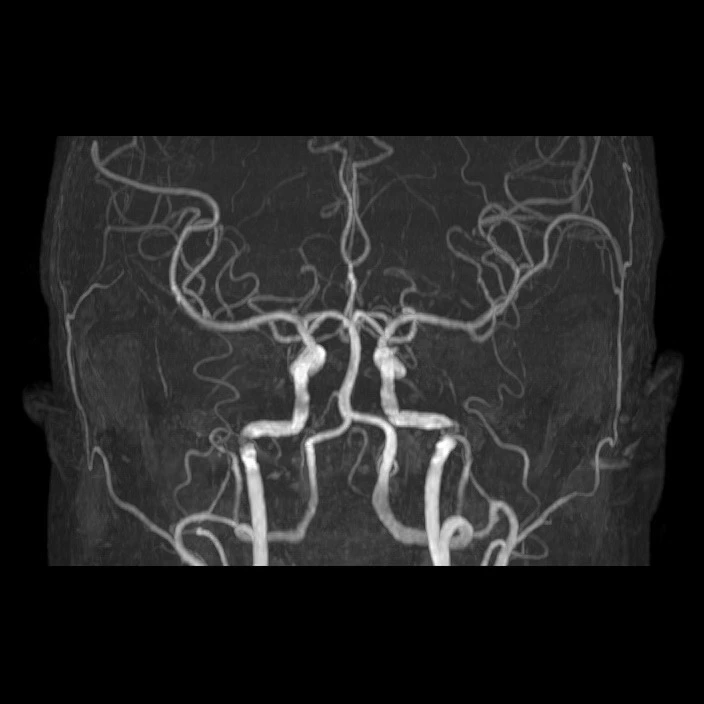

Brain MRA : 뇌혈관 자기공명영상 - 뇌혈관 상태 확인

Diffusion MRI (급성기 뇌손상 확인을 위한 MRI),

Brain MRA (뇌혈관 자기공명영상),

Carotid MRA (좌우 경동맥 자기공명혈관촬영)

이렇게 여러 종류의 MRI 촬영을 했네요!

영상을 보면.. 위에서, 옆에서, 밑에서.. 여러 각도에서 입체적으로 찍었어요.

3D로 뇌혈관, 심장으로부터 목으로 연결되는 경동맥도 잘 보이고,

내 뇌 구조가 이렇게 생겼구나! 정말 신기하더라고요!!

혈관 모습도 좌우 다 다르고 (당연한거지만 신기해서)

Brain MRA (Magnetic Resonance Angiography) : 뇌혈관 자기공명영상. 뇌 속 혈관이 좁아졌거나 막혔는지, 이상 혈관이 있는지 보는 검사.

Carotid MRA (e) : 좌우 경동맥 자기공명혈관촬영을 의미하며, 목의 주요 혈관 상태를 확인해서 뇌로 가느 혈류가 막히거나 좁아진 곳이 없는지 보는 검사. 필요하면 조영제를 사용해 혈관 상태를 더 선명하게 보는 검사.